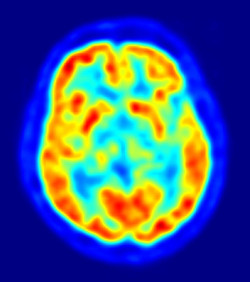

Un equipo interdisciplinar de investigadores, dirigido por las universidades de Cambridge (Reino Unido) y Tubinga (Alemania), ha reunido mediciones del tamaño del cuerpo y el cerebro de más de 300 fósiles del género Homo encontrados en todo el mundo. Combinando estos datos con una reconstrucción de los climas regionales del mundo durante el último millón de años, han identificado el clima específico que experimentó cada fósil cuando era un ser humano vivo.

Una investigación en ratones ha revelado cómo un subconjunto de células inmunes altamente especializadas modulan el cableado cerebral mediante sinapsis inhibidoras dirigidas con precisión. El trabajo profundiza la comprensión del repertorio versátil de microglia, las células inmunes del cerebro y los recolectores de basura residentes. Los resultados sientan las bases para el desarrollo de terapias para afecciones psiquiátricas y del neurodesarrollo marcadas por defectos en la función sináptica.